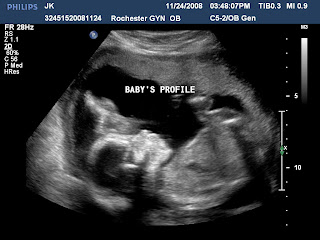

Here are a few pictures of our sweet baby at 20 weeks...